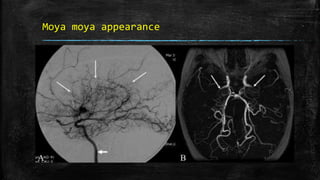

Moya moya appearance

• #92 Moya moya appearance. Lateral anterior oblique view (A) of an internal carotid artery (thick short arrow) angiogram shows multiple, small, tortuous collateral vessels in the distribution of the middle cerebral artery (arrows), suggestive of the moya moya (puff of smoke) appearance. Axial view of the MRI angiogram (B) shows complete occlusion of the middle cerebral arteries bilaterally. Arrows indicate the internal carotid arteries